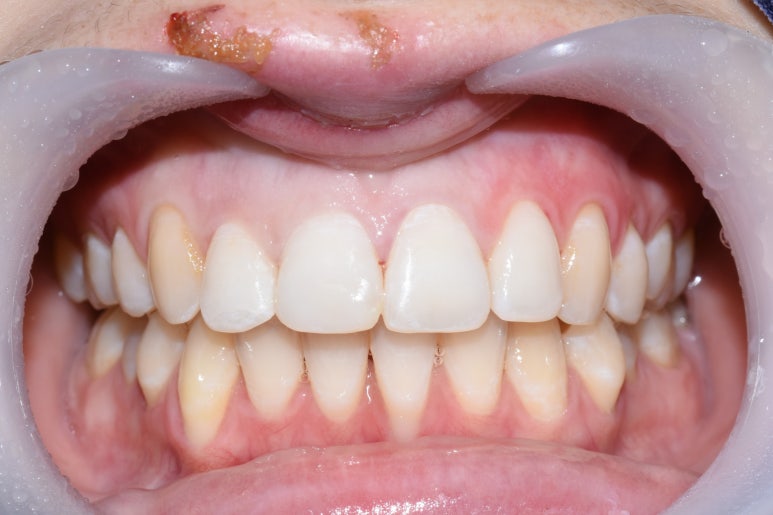

회사생활을 위해 임시로 급하게 앞니를 떼운 모습 (왼쪽) -> 깨진 앞니 크라운을 완성한 상태

넘어져서 앞니가 많이 깨져서 오셨는데

치료를 물론 받으셔야 하지만 회사에서 점심시간에 잠깐 나오신 거라

사회생활을 하기 위해 임시로 앞니를 떼워드린 후

치료를 진행하여 앞니 크라운이 완성되었습니다.

깨진 치아 크라운을 하시는 김에

삐뚤었던 앞니를 교정하는 효과와 치아 색을 더 밝게 하는 효과를 넣어드려서

2개만 치료했지만

나머지 치아들도 더 전반적으로 깔끔해 보이는 효과가 생겼습니다.